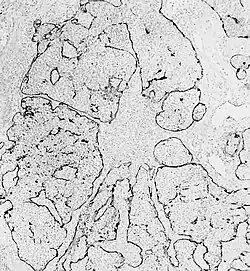

![]() Obraz mikroskopowy nerwiaka węchowego zarodkowego | |

Mikroskopowo guza zalicza się do grupy nowotworów drobnookrągłoniebieskokomórkowych, i wymaga różnicowania z innymi nowotworami należącymi do tej grupy. Komórki nowotworu są małe, o skąpej cytoplazmie, z hiperchromatycznymi jądrami komórkowymi i o drobnoziarnistej chromatynie. Niekiedy tworzą rozetki typu Homera Wrighta albo (rzadziej) Flexnera-Wintersteinera. Podścielisko guza tworzy pilśń neuronalna, utworzona przez wypustki neuronalne komórek nowotworowych. W źle rokujących przypadkach obecne są pola martwicy.